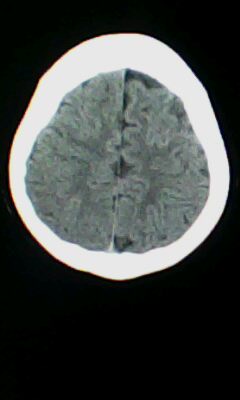

标题: CT25338:女 14岁 3岁时检查为脑积水 现在发育滞后 偶有尿失 [打印本页]

标题: CT25338:女 14岁 3岁时检查为脑积水 现在发育滞后 偶有尿失

颅脑ct轴位平扫颅内未见明确异常。

脑皮质增厚,发育异常!

左侧灰质异位

建议mri

颅脑ct轴位平扫颅内未见明确异常,建议mri。

左侧颞枕叶区密度异常?